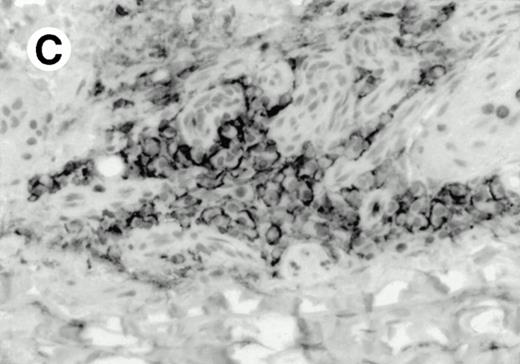

Both paraffin-embedded tissues and frozen sections (with or without heat antigen retrieval) were prepared for immunohistology as described in Materials and Methods. KPL1 stained numerous T cells in the T-zone (TZ) of a human tonsil (Fig 8A), but did not stain B cells in the mantle zone (M) or germinal center (GC) of the secondary follicles. Macrophages in the germinal center stained but follicular dendritic cells did not (Fig 8A). Just outside the germinal center, intense KPL1 staining of overlying plasma cells was observed. A high-power magnification (Fig 8B) shows this intense staining of plasma cells which surround the germinal centers. Subepithelial plasma cells also stained with KPL1 (data not shown), as did plasma cells around vessels in the skin (Fig 8C); these plasma cells costained with the plasma cell marker VS38 (Fig 8D). Thus, B cells located in germinal centers either lack the KPL1 epitope, or express it at levels which are not detected by these methods, whereas plasma cells in numerous sites express high levels. Similarly, four IL-6–dependent human myeloma cell lines expressed high levels of the KPL1 epitope (Diane Jelinek, personal communication, March 1997). Both cortical and medullary lymphocytes in the thymus stained with KPL1 (data not shown). Langerhans cells, bone marrow–derived antigen presenting cells which reside in the suprabasilar region of the epidermis, were also positive for KPL1 (Fig 8E). Langerhans cells in the tonsillar epithelium also stained with KPL1 (data not shown). Langerhans cells in soft tissue also stain with both KPL1 (Fig 8F) and CD1a (Fig 8G).

Expression of PSGL-1 in human tissues. (A) Paraffin tonsil stained with KPL1. The vast majority of the lymphocytes in the T-cell zone (TZ) show dark staining, while the B-lymphocytes in the mantle (M) and germinal center (GC) do not stain. (B) A high magnification of paraffin embedded tonsil stained with KPL1. Plasma cells adjacent to the overlying epithelium show dark membrane staining. The mantle B lymphocytes in the right lower corner do not stain. (C) Plasma cells near vessels in skin stain well with KPL1. (D) Costaining of the cells in (C) with VS38 confirms their identification as plasma cells.